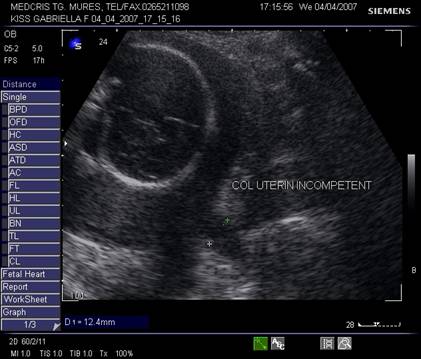

Ecografic canalul cervical apare ca o zona hipoecogena in "V" sau "U", in sectiune sagitala. [1]

Fig. nr.235. Col incompetent la 24 saptamani, se remarca forma de V , la nivelui orificiului cervical intern, intre calipere